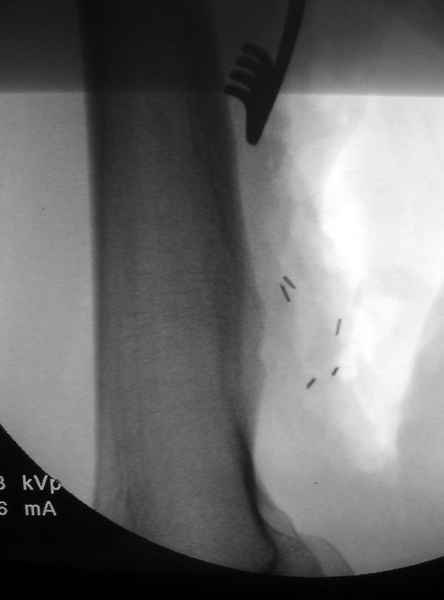

áÎÇÉÏÇÒÁÆÉÑ ÐÏÄÔ×ÅÒÄÉÌÁ ×ÁÓËÕÌÑÒÎÕÀ ÁÎÅ×ÒÉÚÍÕ × ÒÅÚÕÌØÔÁÔÅ ÄÁ×ÌÅÎÉÑ

ÜËÚÏÓÔÏÚÏÍ. óÏ×ÍÅÓÔÎÏ Ó ÓÏÓÕÄÉÓÔÙÍ ÈÉÒÕÒÇÏÍ ÂÙÌÁ ÐÒÏ×ÅÄÅÎÁ

ÐÌÏÓËÏÓÔÎÁÑ ÒÅÚÅËÃÉÑ Ó ÄÁÌØÎÅÊÝÉÍ ×ÏÓÓÔÁÎÏ×ÌÅÎÉÅÍ ÓÏÓÕÄÁ ×ÅÎÏÚÎÙÍ

ÇÒÁÆÔÏÍ.

éÍÑ     : #20 vascular work 12.jpg

éÍÑ     : #22 osteochondroma.jpg

éÍÑ     : #24 bone work 1.jpg